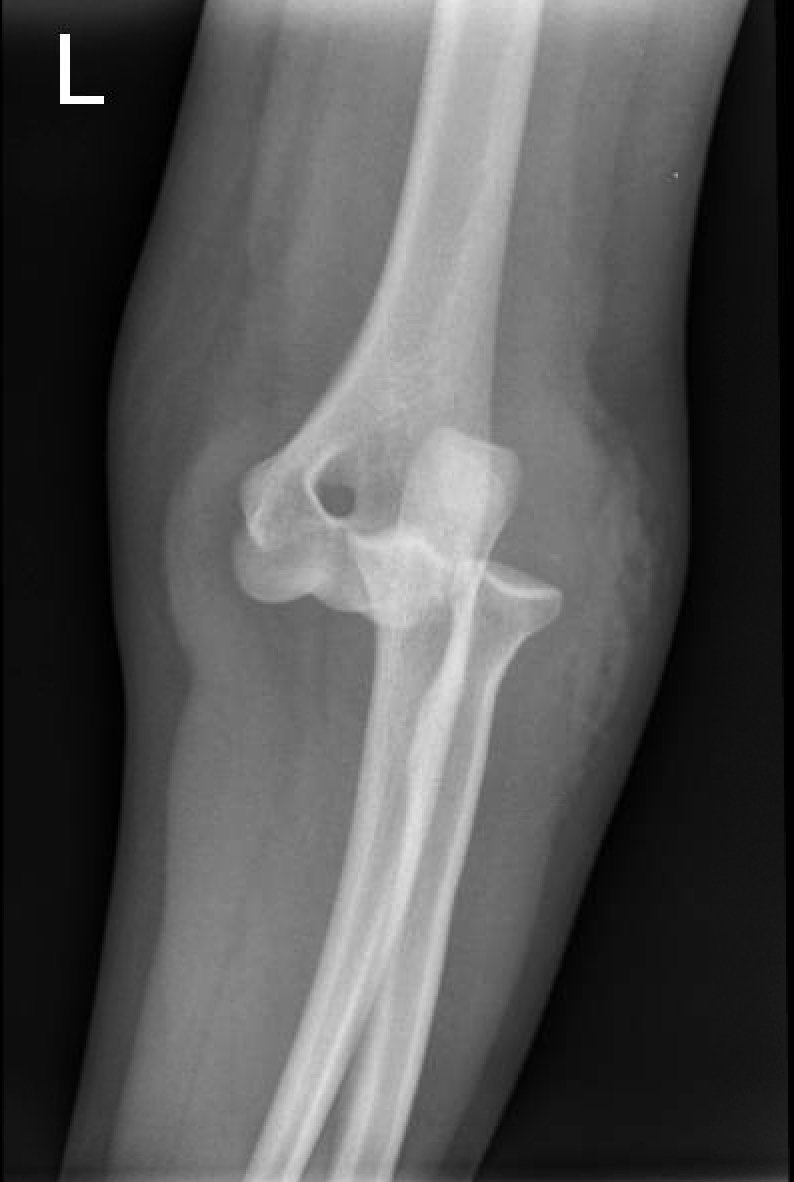

Posterior Elbow Dislocation, Oblique XRay, dislocated. JETem 2016